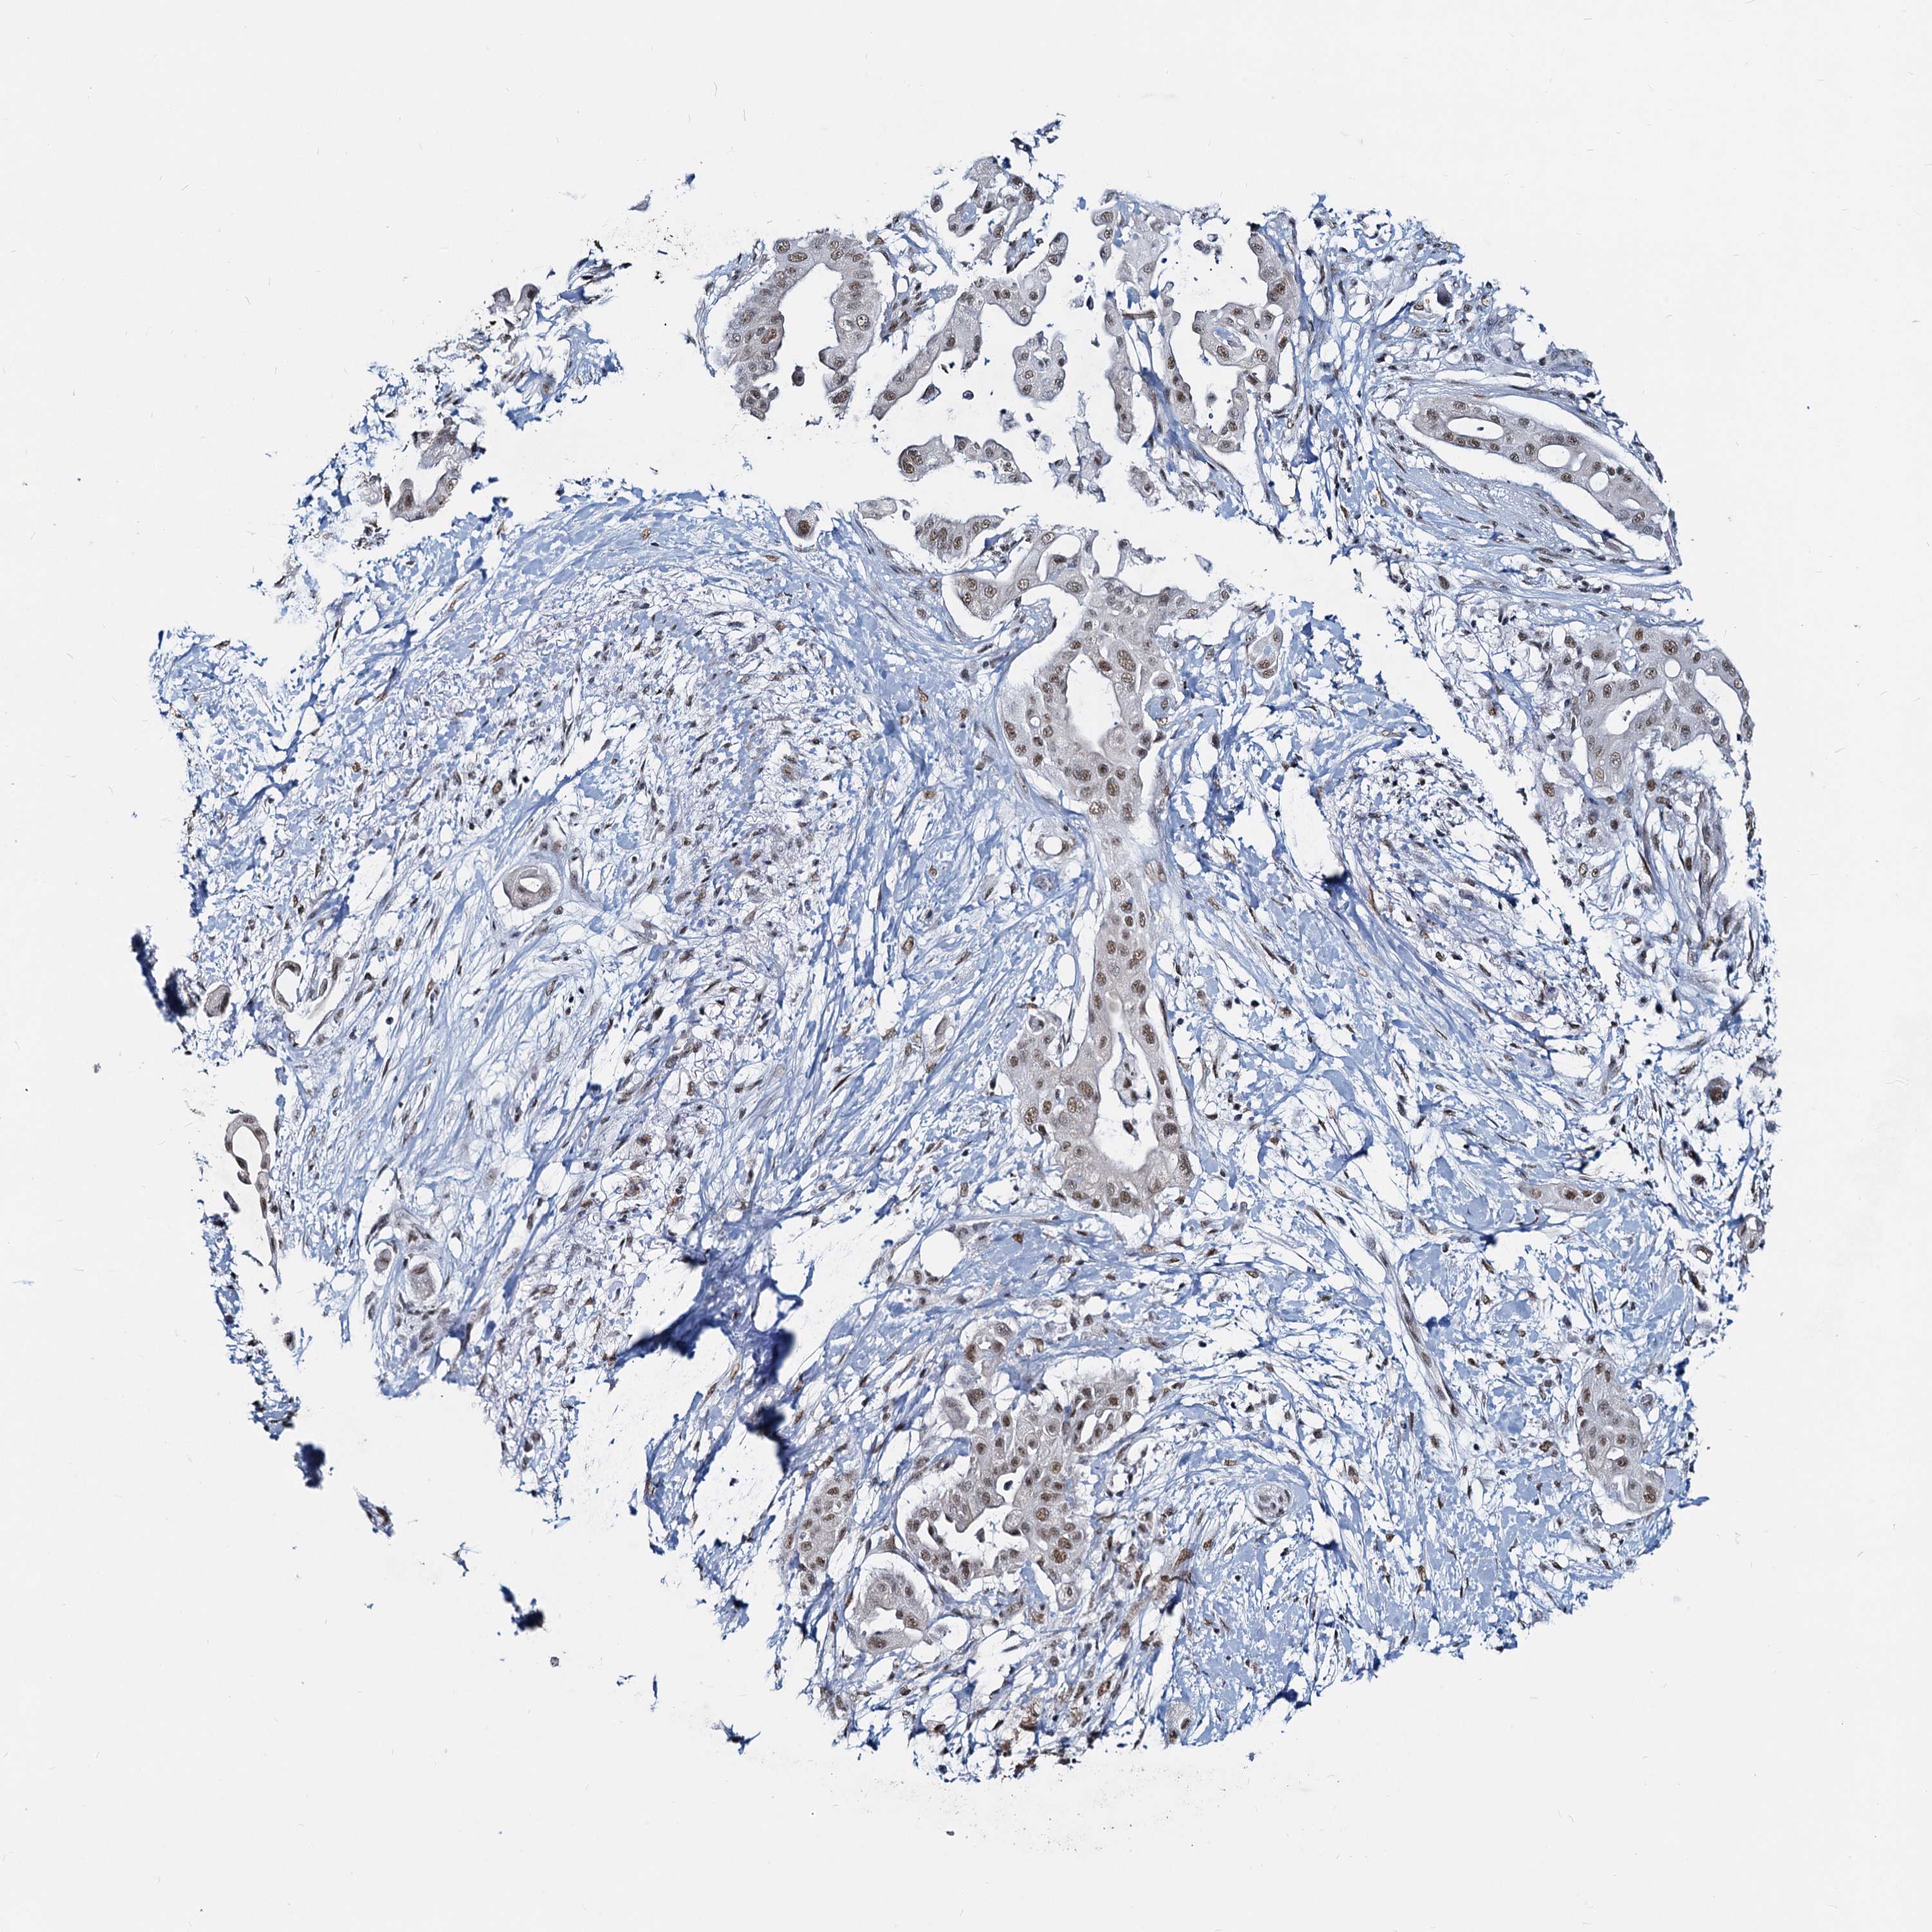

PANCREATIC CANCER - Protein expressioni

A mouse-over function shows sample information and annotation data. Click on an image to view it in a full screen mode. Samples can be filtered based on level of antibody staining by selecting one or several of the following categories: high, medium, low and not detected. The assay and annotation is described here.

Note that samples used for immunohistochemistry by the Human Protein Atlas do not correspond to samples in the TCGA dataset.

Antibody stainingi

Antibody staining in the annotated cell types in the current human tissue is reported as not detected, low, medium, or high, based on conventional immunohistochemistry profiling in selected tissues. This score is based on the combination of the staining intensity and fraction of stained cells.

Each image is clickable and will lead to virtual microscopy that enables deeper exploration of all samples and also displays staining intensity scores, fraction scores and subcellular localization as well as patient and tissue information for each sample.

Antibody HPA038002

Staining

High

Medium

Low

Not detected

Intensity

Strong

Moderate

Weak

Negative

Quantity

>75%

75%-25%

<25%

None

Location

Nuclear

Cytoplasmic/membranous

Cytoplasmic/membranous,nuclear

Adenocarcinoma, NOS